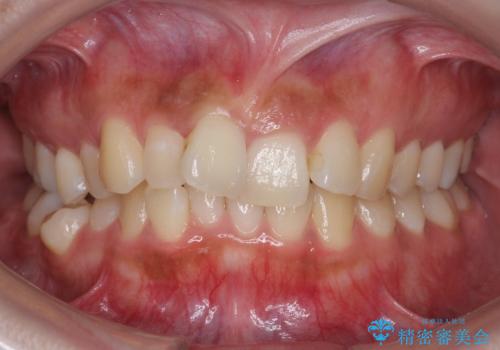

- 前歯のがたつきを主訴に来院。

前歯は目立つのでワイヤー矯正は絶対にしたくないとのことでした。

右上の奥歯を後ろに送り、前歯が出っ歯にならないように並べました。

また、右下の奥歯に一部目立たないように部分的なワイヤー矯正を行い、右下の奥歯が反対咬合になっていたのもしっかり中に入れて治療しています。